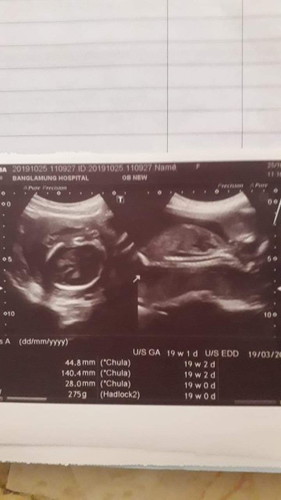

19วิดเเร้วเรายังไม่รุ้เรยว่าลูกเราเป้นยังไงบ้าง ตอนหมออัลตร้าซาว์ แม่ๆท่านไหนเป้นบางค่ะ

เดาว่าภาพซ้ายน่าจะเป็นกระโหลกค่ะ แต่ไม่แน่ใจเลยค่ะ มันไม่ชัดเท่าไหร่ ส่วนภาพขวา ดูไม่ออกจ้า